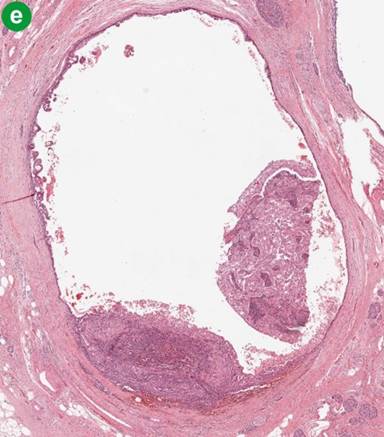

Microscopy revealed that the main bulk of the tumor was cystic/hemorrhagic and located within the uncinate process. At the same time, the tumor was intimately related to the main pancreatic duct and its branches. It grew along their lumen as an intraductal, pencil like growth and protruded into the lumen of the duodenum, forming a polypoid structure. Both components (cystic and intraductal) were predominantly comprised of non-epithelial component: pleomorphic large cells, histiocyte-like mononuclear cells, atypical mononuclear cells and spindle cells with multiple, atypical and bizarre mitoses, as well as osteoclast-like giant cells (Figure 3a). Extensive sampling of the tumor revealed a minor epithelial component (Figure 3bcd), showing glandular differentiation within the intraductal pencil-like growth present in the main pancreatic duct and its branches (Figure 3ef), as well within the cystic component.

Figure 3. Histomorphologic findings. a. Mixture of the pleomorphic large cells, histiocyte-like mononuclear cells, atypical mononuclear cells and osteoclast-like giant cells (H&E, original magnification 20x). b. As above, but mixed with epithelial neoplastic cells (H&E, original magnification 20x). c. and d. Epithelial neoplastic cells strongly positive for pankeratin and cytokeratin 34 beta E12 (original magnification 20x). e. Early intraductal growth of the undifferentiated carcinoma of the pancreas (H&E, original magnification 2x). f. Pancreatic duct almost completely occluded by intraductal growth of the undifferentiated carcinoma of the pancreas (H&E, original magnification 2x). |

Two growth patterns were appreciated: invasive growth and intraductal extension. The former was large, hemorrhagic cysts, representing a necrotic/degenerative process. The cysts were hemorrhagic, usually devoid of lining, and surrounded by a mesenchymal (non-epithelial) neoplastic component. There was a significant proportion of osteoclast-like giant cells, large pleomorphic cells, and hemosiderin, usually without an epithelial neoplastic component. However, extensive sampling demonstrated remnants of epithelial lining indicating its relation/origin to the branches of the main pancreatic duct. The latter pattern was intraductal/intraluminal neoplastic growth/extension within dilated branches of main pancreatic duct with preserved epithelial lining (Figure 3e). Various degrees of pancreatic duct involvement (morphological heterogeneity), ranging from minimal intraluminal growth to complete occlusion of the lumen were noted. The cytologically abnormal epithelial lining within early intraductal involvement was focally lifted up and intermingled with the non-epithelial neoplastic component. The intraductal growth partially involving the lumen seems to be the finding of the tumor front, which represents the mode of early involvement of the duct by the tumor. It was clear that prominent intraductal extension of the tumor is an important and unique feature of this case.